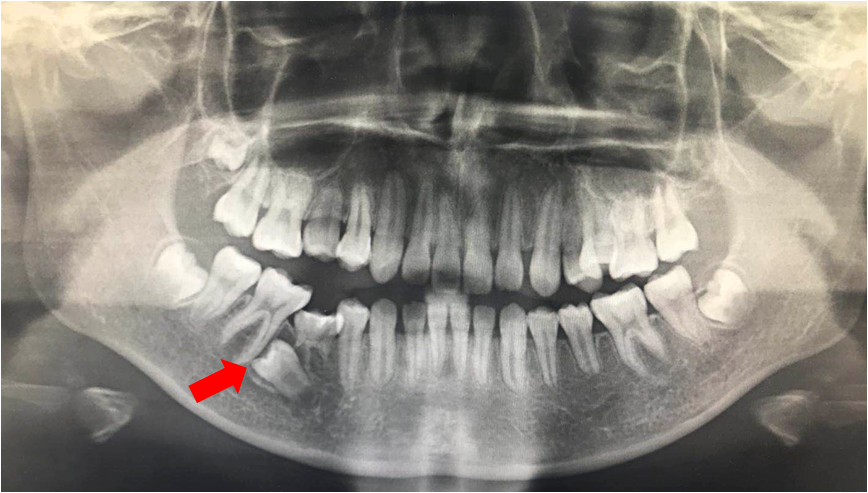

小方今年小学四年级,和别的孩子一样,过着无忧无虑的生活,但最近学校体检结果却让他的全家忧心忡忡。原来,小方右上乳门牙掉了三年多,一直没有生长的迹象。正巧,有同班同学在同济大学附属口腔医院做早期矫治。小方一家赶在过年前来到了正畸科进行了详细的检查。医生发现,小方右上中切牙、侧切牙、尖牙口腔内都未见到,右上还有个中度松动的乳尖牙。 医生给小方进行了X片的拍摄,发现小方右上三颗前牙在牙槽骨内包绕成球状,互相制衡,难怪一直长不出! 医生说,小方这种情况属于“埋伏牙”,在人群中发生率为4-14%,而像小方这种三颗牙都没有萌出的情况尤为少见。那么接下去该如何治疗呢?医生提议,小方这种情况需要尽早把埋伏的牙齿一颗一颗牵引到口腔中,以免产生更严重的后果。但是,治疗时间较长,预计两到三年,而且存在牙根吸收、牙齿牵出后牙齿可能存在少量松动等情况。经考虑再三,为了防止小方门牙以后做“假牙”,家属一致同意进行治疗。 在治疗中,医生给小方拍摄了三维的CBCT,通过三维重建,明确每一颗牙的生长方向以及毗邻关系,确定正畸牵引的先后次序。然后,和口腔颌面外科医生合作,明确埋伏牙开窗部位、顺序以及时间。经过一段时间的努力,小方的牙齿一颗一颗奇迹般的生长而出。 经过一年半的治疗,小方的右上尖牙以及侧切牙顺利纳入牙弓;CBCT显示,右上中切牙处于腭向位,需要唇向牵引。又经过一年的矫治,三颗牙总算恢复到牙弓内了。 无独有偶,小王由于乳牙长期未脱落,而到医院检查,意外发现右下第二前磨牙横躺在牙槽骨中。X片显示右下第二前磨牙水平向阻生,牙根发育仅为正常同名牙的一半,右下第一磨牙牙冠倾斜。 无疑,小王这个情况也比较复杂,不治疗的话,这颗埋伏牙牙根发育有问题,将来面临着拔除的风险,而治疗,则意味着持久作战的可能。最后,经过正畸医生、儿童口腔医生、口腔外科医生团队的通力合作,以及小王的密切配合,花了将近一年多的时间,总算把这颗埋伏牙安装到了正确的位置。 那么如何判断孩子牙齿萌出是否正常呢? 1、多数情况下,牙龄和生理年龄存在一定关联,上下四颗切牙在7-8周岁萌出,而尖牙、前磨牙往往在9-11周岁生长。 2、下牙萌出早于上牙。 3、两侧同名牙萌出时间较为同步。 若发现孩子牙齿萌出障碍,需要尽早至口腔正畸科进行检查,以免错失治疗最佳时机。 同济大学附属口腔医院正畸科 撰稿:赵彦惠 审校:廖崇珊 延伸阅读